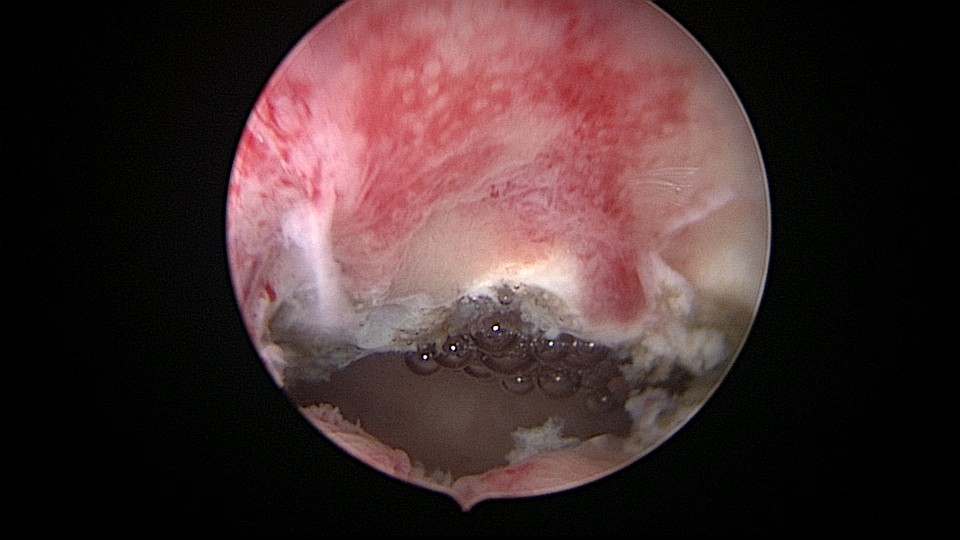

患者32岁,G2P0,自然流产2次,外院行清宫术,术后月经量减少一半。2019年6月市妇幼分粘,术后月经无改善,宫腔粘连复发,2020年11月宫腔镜探查,宫腔中上段幕状粘连,形成两个假的输卵管开口,双极电针分粘,恢复宫腔形态,显露正常的输卵管开口。2020年12月宫腔镜二探取球囊,宫腔形态正常,双侧输卵管开口可见,内膜充血。2022年5月自然妊娠,2023年1月剖宫产分娩一女婴(37+2)。现37岁,G3P1。